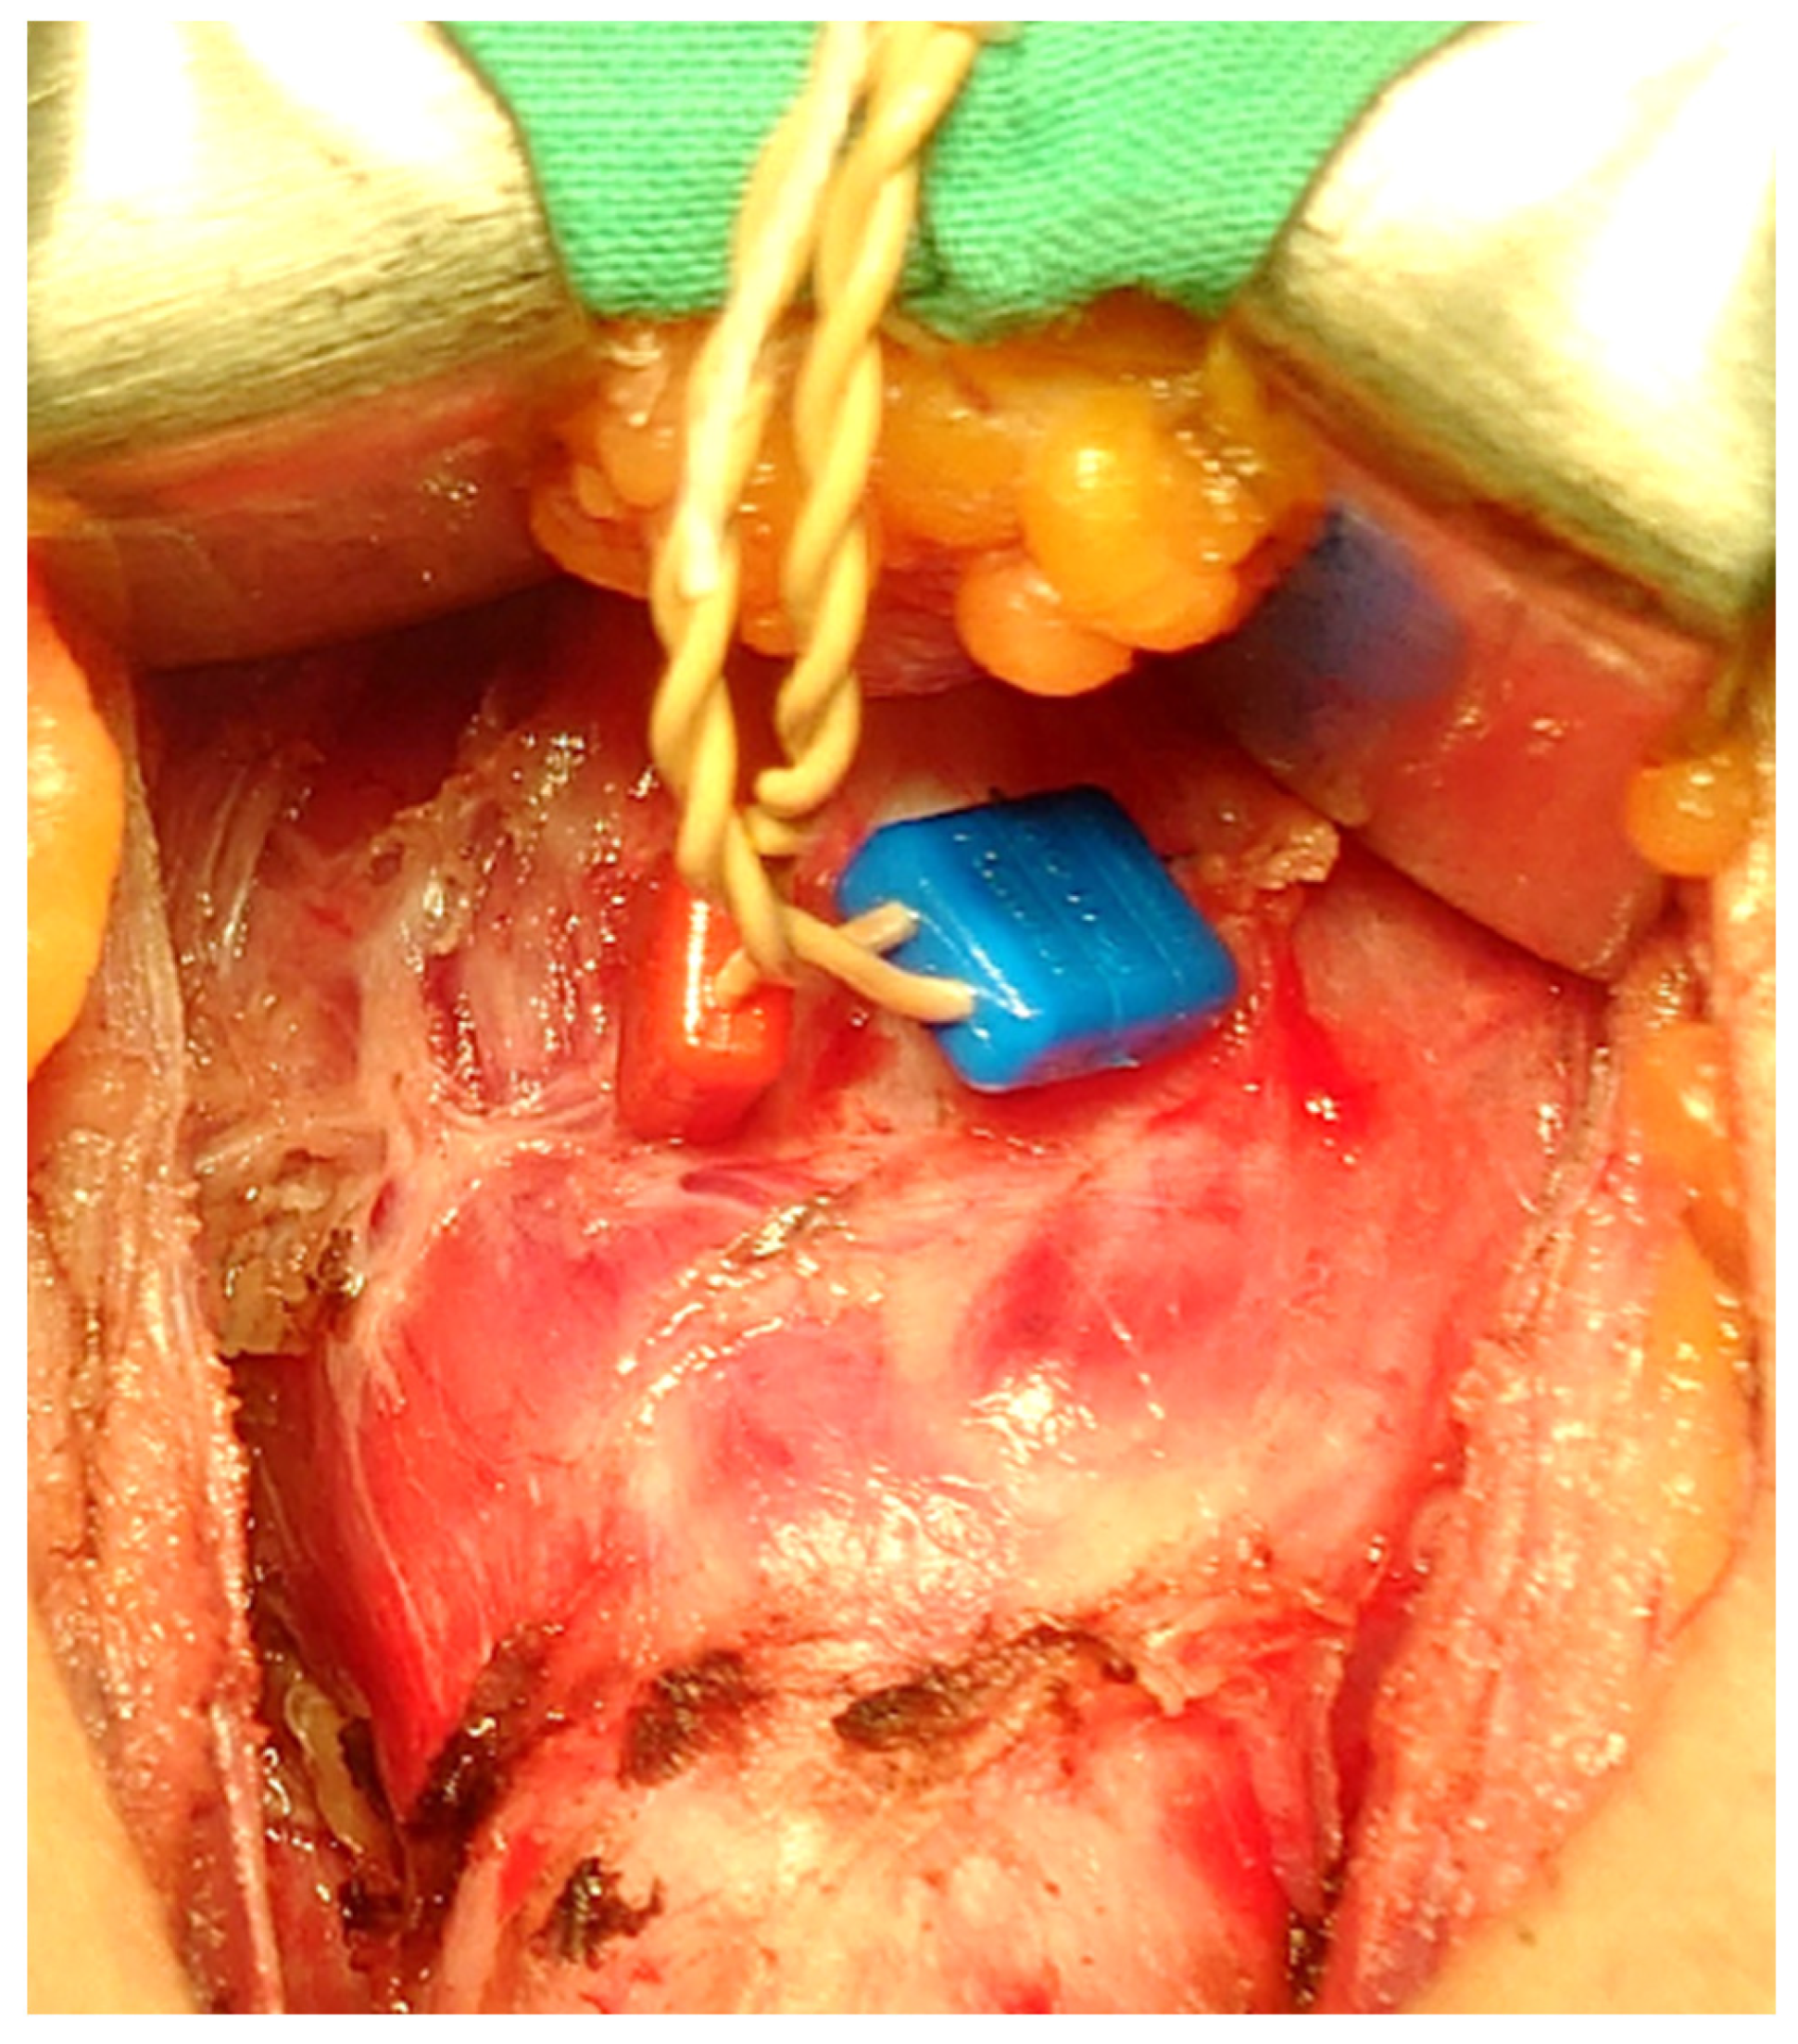

- Huang, T.Y.; Kim, H.Y.; Dionigi, G.; Lu, I.C.; Chang, P.Y.; Chiang, F.Y.; Lin, Y.C.; Tseng, H.Y.; Liu, C.H.; Wu, C.W. Laryngeal Neural Monitoring during Pediatric Thyroid Cancer Surgery-Is Transcartilage Recording a Preferable Method? Cancers 2021, 13, 4051. [Google Scholar] [CrossRef] [PubMed]